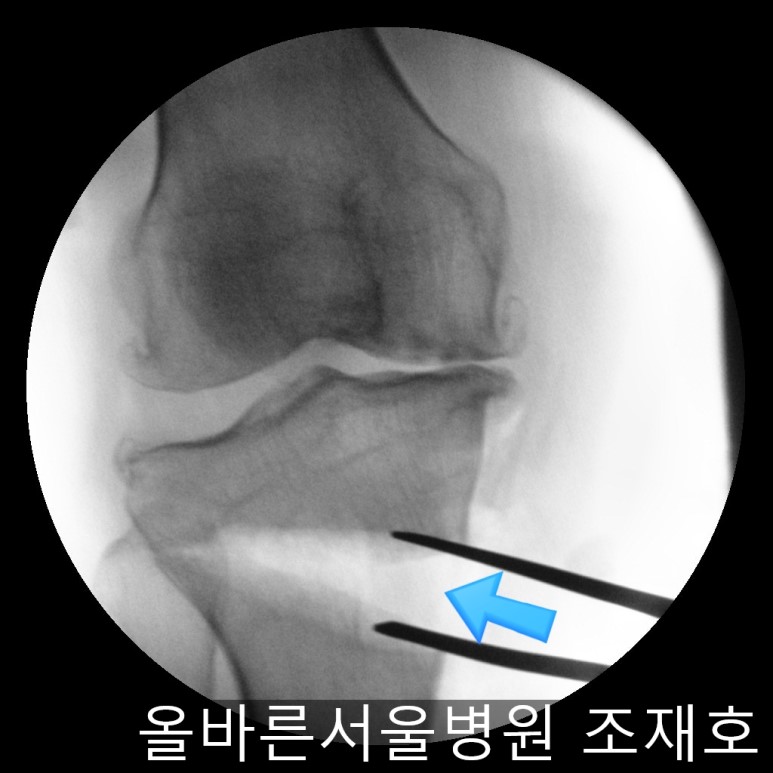

随后进行胫骨近端截骨术来矫正内翻变形。

需要进行20度矫正,因为没有这个度的矫正用模具,所以在手术前先计算内侧需要打开的程度。

如下图,适当的打开进行矫正。

之后用骨替代物填充,确认固定。

确保正面准确矫正。

侧位影响中也没有slop增加,矫正成功。